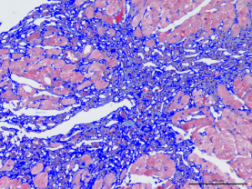

组织病理学平台

利用Image-pro-plus对病理染色结果半定量分析

利用Image-pro-plus软件,可以为您对各种动物疾病模型采取针对性染色,并对染色结果给出半定量分析,包括但不限于以下疾病模型:

2肝纤维化模型胶原纤维半定量分析